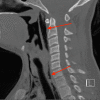

A Case of Spontaneous Pneumomediastinum Following Ecstasy and Marijuana Use

Spontaneous pneumomediastinum (SPM) is a benign and self-limiting condition more commonly seen in young adults. Radiology imaging of the chest, including X-ray or CT scan, is the gold standard for diagnosis. Ecstasy, also known as 3,4-methylenedioxymethamphetamine (MDMA) is a synthetic amphetamine derivative widely abused for an increased sense of well-being and euphoria. Marijuana is also abused for recreational purposes. SPM has been reported after both Ecstasy and marijuana use. SPM after these illicit drugs abuse usually has a benign and self-limiting course with supportive management. However, it is always important to rule out serious associated conditions like esophageal perforation. Here, we present a 22-year-old male who developed SPM after Ecstasy ingestion and marijuana inhalation.